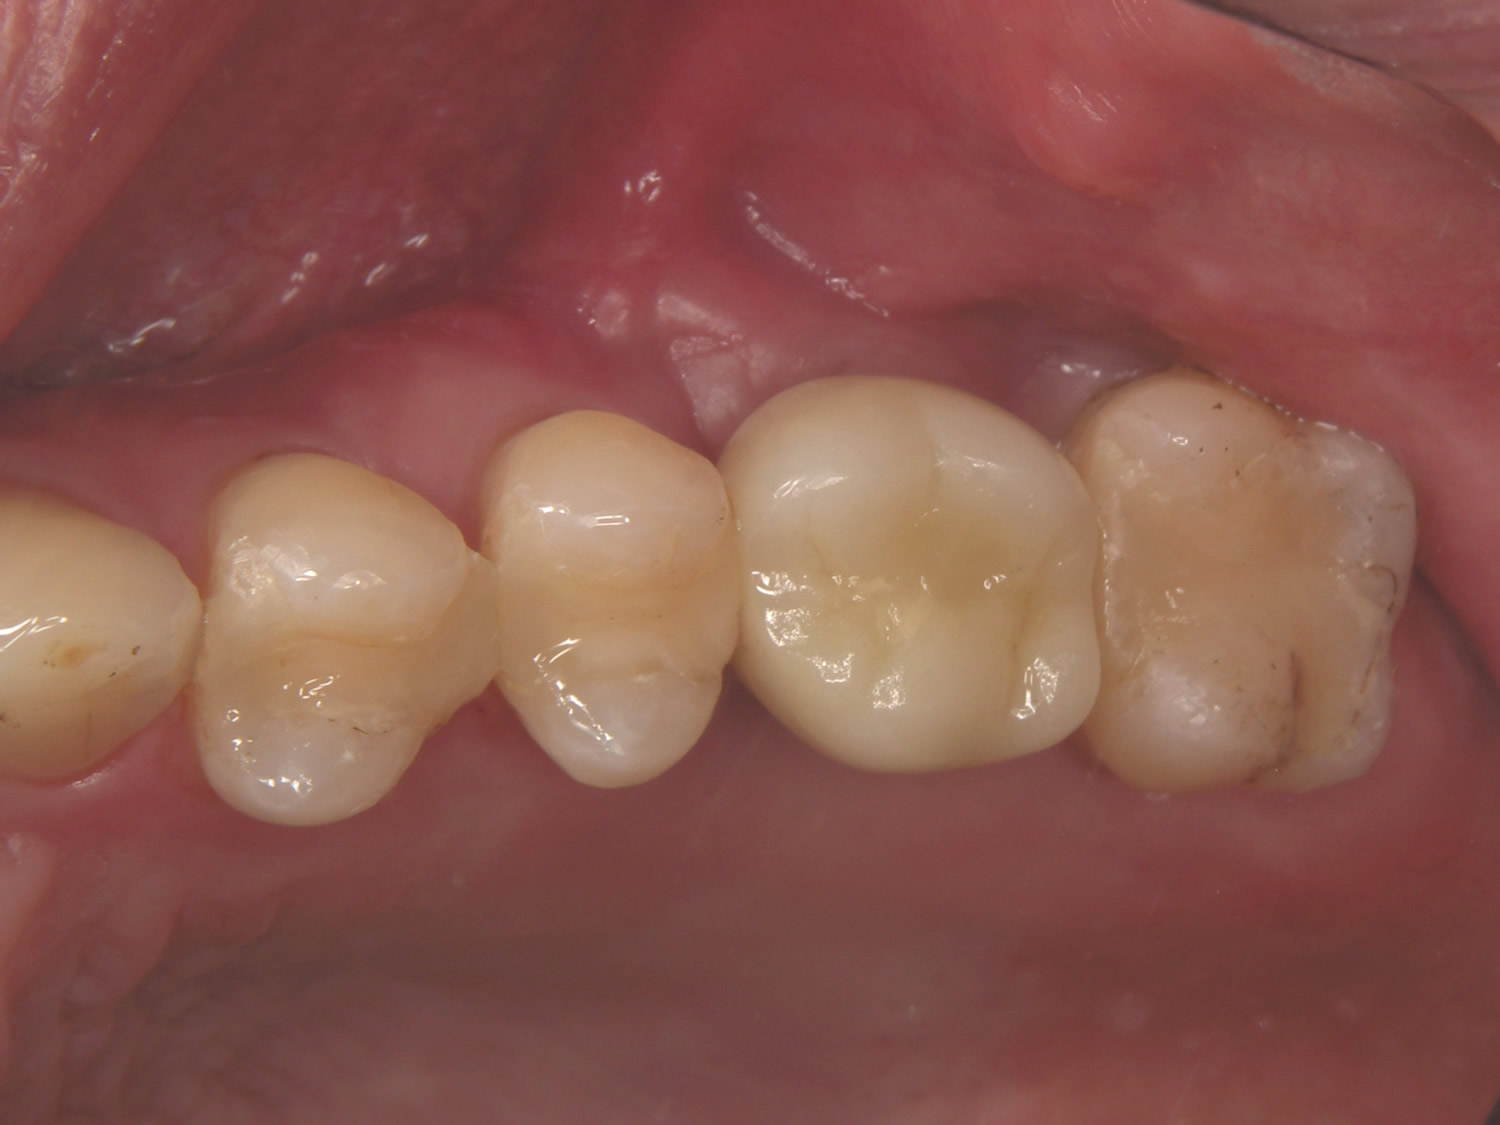

最終補綴物装着時口腔内写真 DT:小見川 純

患者様も大変満足されました

最終補綴物装着時口腔内写真 拡大1

最終補綴物装着時口腔内写真 拡大2

最終補綴物装着時口腔内写真 拡大3

最終補綴物装着時口腔内写真 拡大4

最終補綴物装着時口腔内写真 拡大5